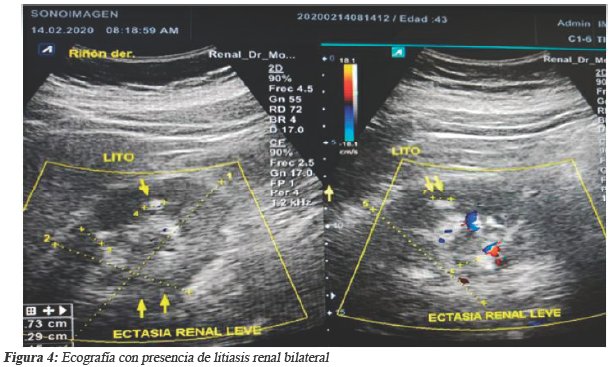

Ante los hallazgos de la colonoscopia-TAC y estudios anatomopatológicos el gastroenterólogo decide comenzar tratamiento con corticoides parenteral, azatioprina y mesalazina oral. Conociendo del caso el radiólogo procede previo el consentimiento del paciente a realizar un estudio ecosonográfico, detectándose un cálculo renal derecho de 5 mm de tamaño y otro de 4 mm en el izquierdo (Ver figura 4).

Los resultados del análisis de orina mostraron aciduria, cristales de oxalato de calcio y la radiografía simple de abdomen mostró sombra de los cálculos.